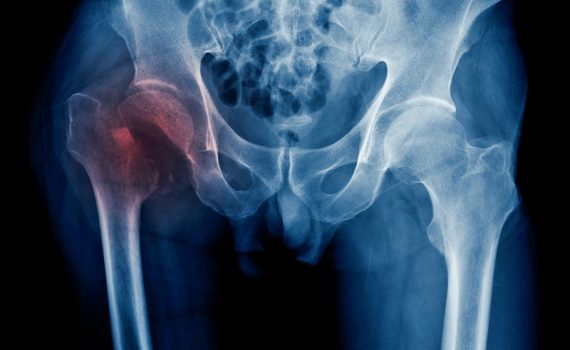

Registro Nacional de Fraturas de Quadril concedido pela OMS

O Registro Nacional Fratura de Quadril (RNFC), recentemente premiado pela OMS, é um projeto cujo objetivo é a obtenção de informações de pacientes que sofrem de fratura de quadril para pesquisa e melhorar sua qualidade de vida. Grupo envelhecimento e fragilidade no Instituto de Pesquisa de idosos no Hospital Universitário de La Paz consiste em mais de 200 profissionais interdisciplinares tem sido reconhecido pela OMS com o prêmio da Fundação para a Promoção da Saúde 2019 Estado do Kuwait, por sua contribuição para a melhoria do cuidado ao idoso. A pesquisa reúne informações sobre essa lesão frequente em idosos, por meio de dados fornecidos por mais de 76 hospitais espanhóis. Ler mais